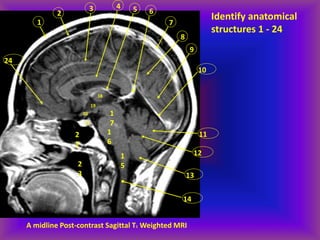

A midline Post-contrast Sagittal T1 Weighted MRI

Identify anatomical

structures 1 - 24

1. Scalp fat

2. Bone

3. Inferior sagittal sinus

4. Corpus callosum

5. Internal cerebral vein

6. Vein of Galen

7. Superior sagittal sinus

8. Parietal lobe

9. Occipital lobe

10. Straight sinus

11. Vermis

12. IV ventricle

13. Cerebellar tonsil

14. Cervical cord

15. Medulla

16. Pons

17. Midbrain

18. Mass intermedia of thalamus

19. Anterior III ventricle

20. Optic chiasm

21. Pituitary gland

22. Sphenoid sinus

23. Nasopharynx

24. Frontal lobe